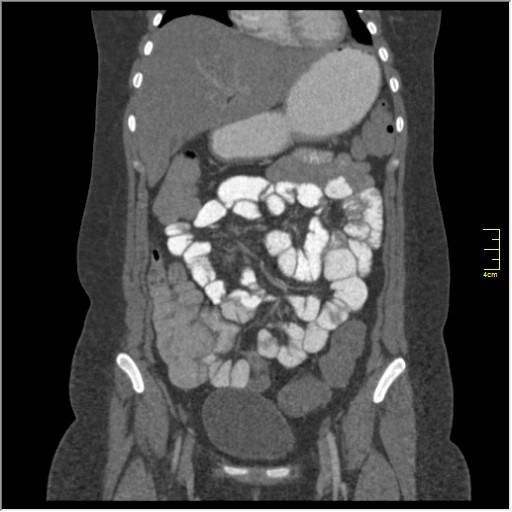

КТ энтерография

Демонстрационные изображение, оцените возможности метода! Толщина среза реконструкции 0.5-1 мм.